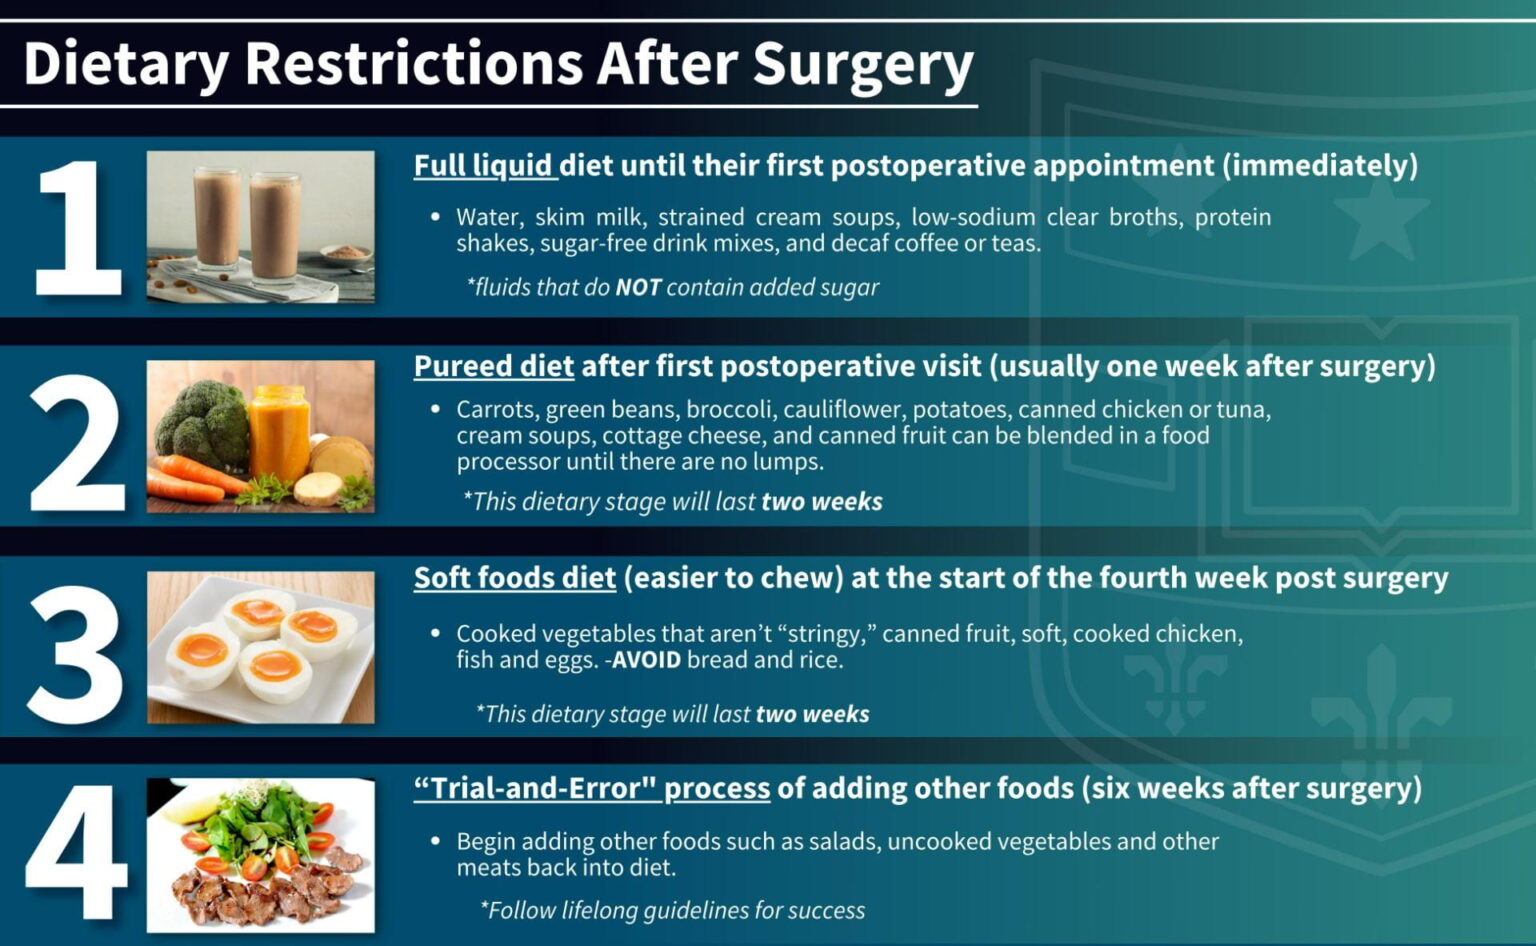

When Can You Eat Solid Foods After Gastric Bypass

When Can You Eat Solid Foods After Gastric Bypass

More picture related to When Can You Eat Solid Foods After Gastric Bypass

Gastric Sleeve Post op Diet Stages Explained One By One Dr Ceyhun

Life After Bariatric Surgery Activities Diet Department Of Surgery

Diet After Gastric Bypass Nutrition Planning

Pin On Gastric Bypass Meal Plan Ideas